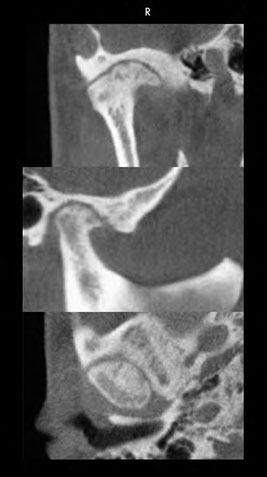

tmj

osteoarthritis